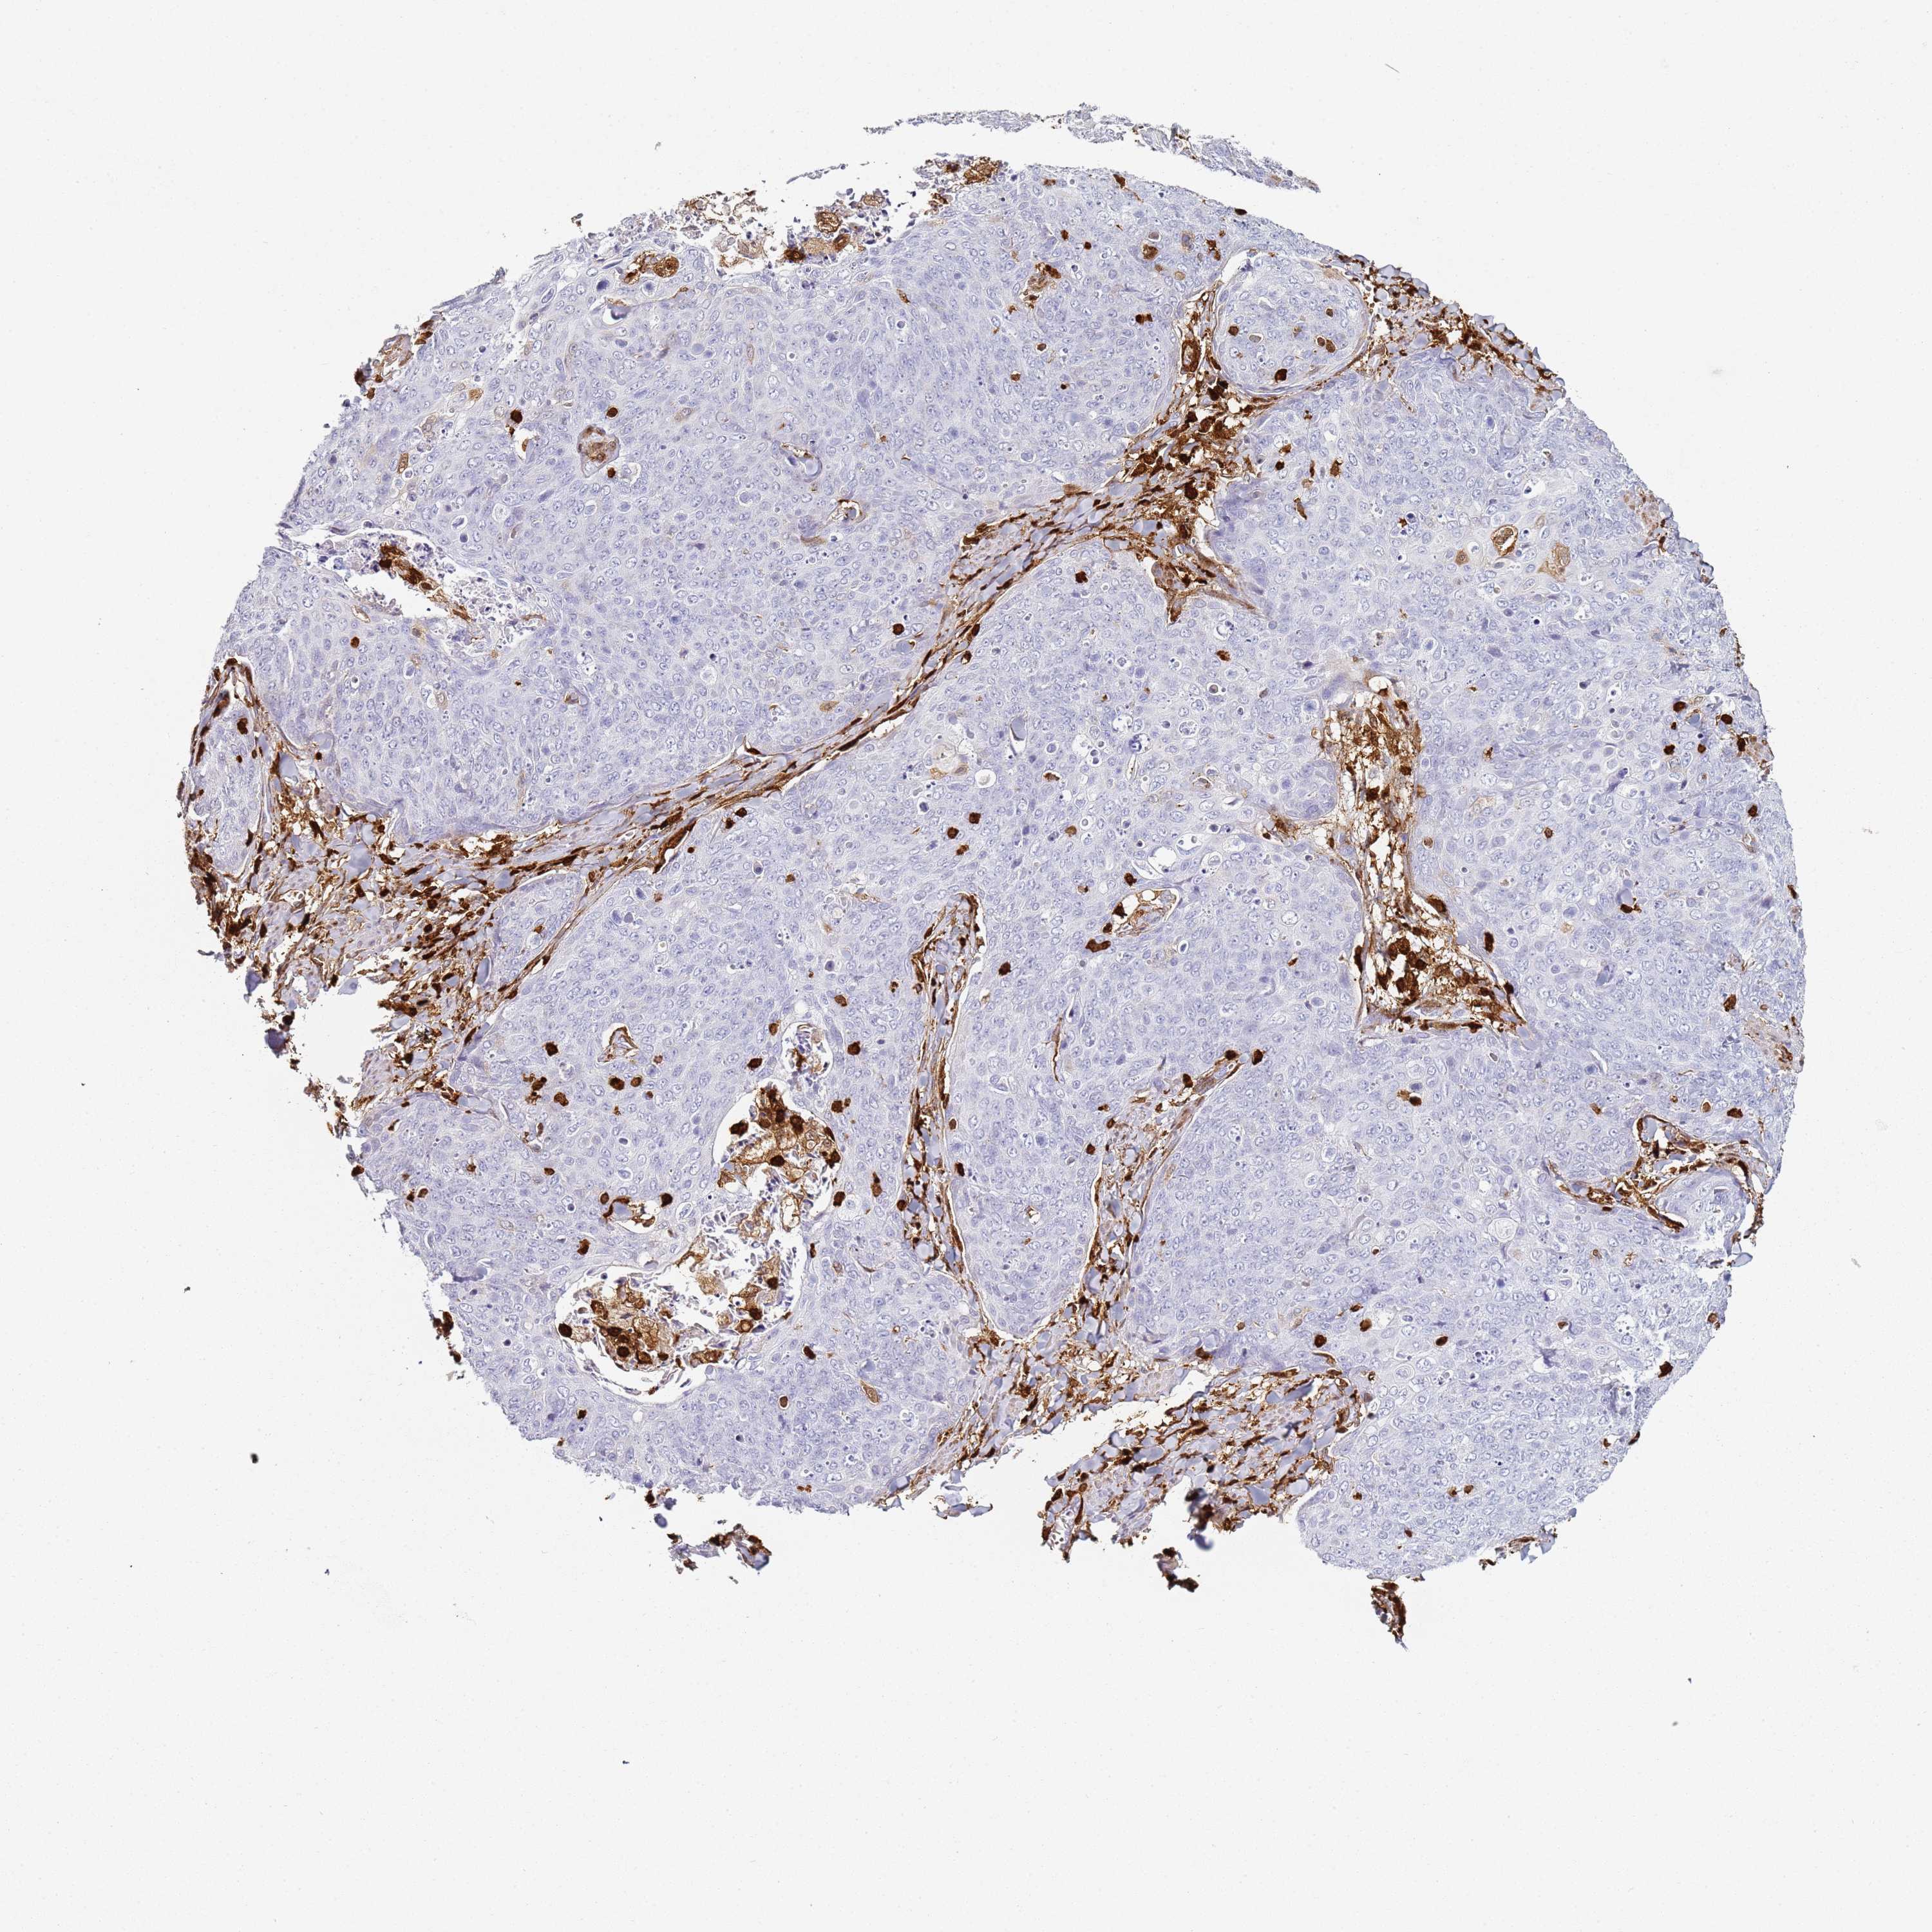

CANCER SKIN CANCER Show tissue menu

Basal cell and squamous cell cancer

SKIN CANCER - Protein expressioni

A mouse-over function shows sample information and annotation data. Click on an image to view it in a full screen mode. Samples can be filtered based on level of antibody staining by selecting one or several of the following categories: high, medium, low and not detected. The assay and annotation is described here.

Each image is clickable and will lead to virtual microscopy that enables deeper exploration of all samples and also displays staining intensity scores, fraction scores and subcellular localization as well as patient and tissue information for each sample.

HPA007973

CAB002618

CAB027387

CAB058698

CAB068227

CAB068228

Basal cell carcinoma

Squamous cell carcinoma, NOS

Squamous cell carcinoma, metastatic, NOS